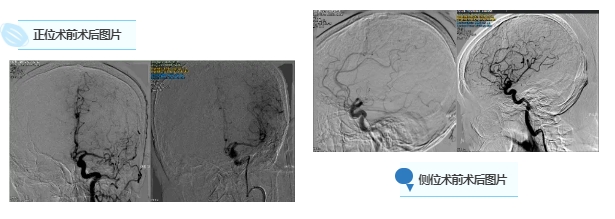

近日,北医三院秦皇岛医院神经血管介入科收治了一位急性脑梗死患者。这位患者在1年前就曾因脑梗死入院接受过保守治疗,出院时并未留下明显后遗症。此次是因为突发右侧肢体瘫痪,且长达1小时无法讲话。入院时,患者状况不佳,已无法配合查体,双眼还向右侧凝视。查看其既往住院记录得知,患者患有高血压以及阵发性心房颤动病史。结合此次发病突然且症状严重的情况,神经血管介入科主任王振兴及值班医师高度怀疑是房颤致使心脏血栓脱落,堵塞了大脑动脉。在详细介绍病情后,建议患者行急诊造影,必要时进行脑动脉取栓术。或许是因为患者此前有在我院就诊的经历,对我科十分信任,毫不犹豫地就同意了手术。神经血管介入科全体医护人员迅速行动,在患者入院短短30分钟内,就成功完成了股动脉穿刺,并完成左侧颈内动脉造影,顺利开通了患者左侧大脑中动脉的闭塞部位。

术后效果立竿见影,患者未下手术台,右侧肢体已经能够轻微抬起,而且可以配合张嘴及摇头动作,双眼球活动自如,令人十分欣慰。到了术后第二天,患者能够下地行走,对话也流利顺畅,出院时患者行动自如,未留下任何后遗症,患者及家属对此次治疗赞不绝口。